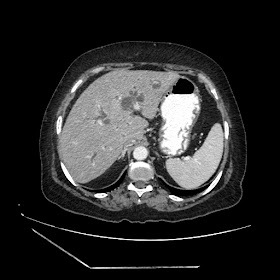

A 70 years old woman with Obstractive jaundice & palpable GB

Latest Radiological images: